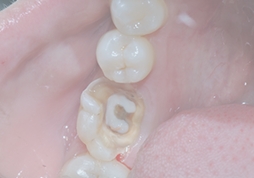

Deep Cavity

Canal Preparation and Disinfection

Open pulp chamber, remove necrotic tissue, then disinfect canals with medicaments.

Canal Filling

Place medicament for 3–5 days to test pain relief, then complete canal filling if stable.